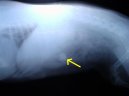

Kostní trus v sestupné části tlustého střeva.